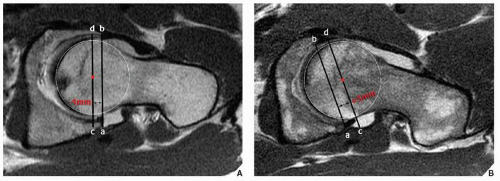

1. Femoro-acetabular impingement (FAI):

The surgical treatment will change with the cause and effects of FAI.

- Cam deformity can be treated with shaving the ‘bump’ at the lateral aspect of the femoro-acetabular junction.

- If there is associated labral tear, then shaving the ‘bump’ + labral repair.

- If there is chondral changes or degeneration then may require shaving the patient may require resurfacing of the hip joint.